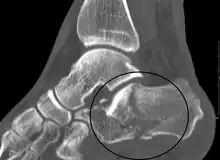

Calcaneal fracture | |

X-ray of a fractured calcaneus | |

Diagnostic method | Based on symptoms, X-rays, CT scan[1] |

Conventional radiography is usually the initial assessment tool when a calcaneal fracture is suspected. Recommended x-ray views are (a) axial, (b) anteroposterior, (c) oblique and (d) views with dorsiflexion and internal rotation of the foot. However, conventional radiography is limited for visualization of calcaneal anatomy, especially at the subtalar joint. A CT scan is currently the imaging study of choice for evaluating calcaneal injury and has substituted conventional radiography in the classification of calcaneal fractures.[13] Axial and coronal views are obtained for proper visualization of the calcaneus, subtalar, calcaneocuboid and talonavicular joints.

The Angle of Gissane, or "Critical Angle", is the angle formed by the downward and upward slopes of the calcaneal superior surface. On a lateral radiograph, an angle of Gissane > 130° suggests fracture of the posterior subtalar joint surface. Böhler's angle, or the "Tuber Angle", is another normal anatomic landmark seen in lateral radiographs. It is formed by the intersection of 1) a line from the highest point of the posterior articular facet to the highest point of the posterior tuberosity, and 2) a line from the former to the highest point on the anterior articular facet. Böhler's angle is normally 25° to 40°.[14] It is named after Austrian physician Lorenz Böhler.[16] A decreased angle is indicative of a calcaneal fracture.